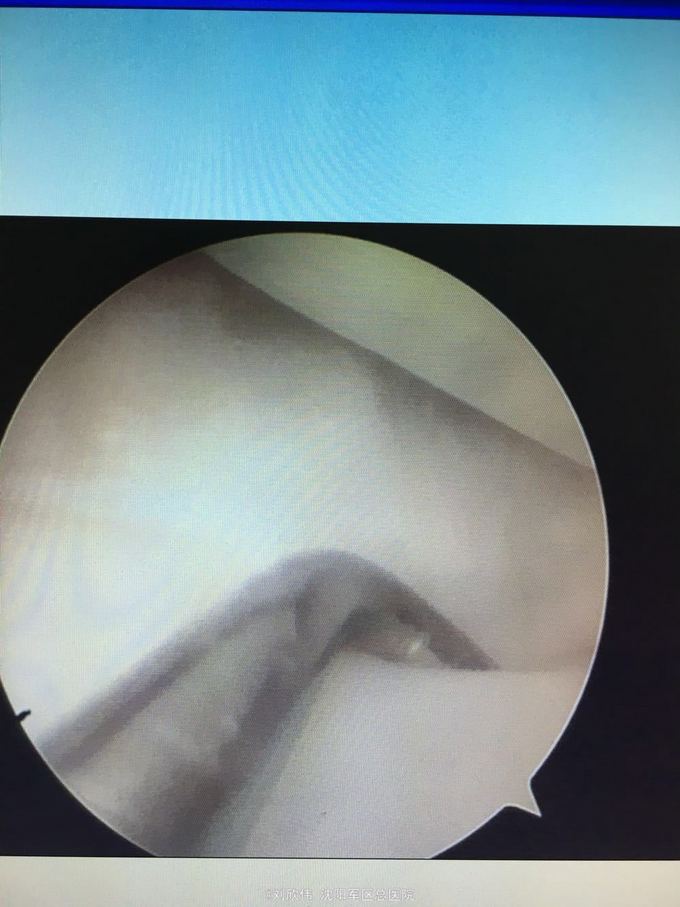

左膝骨软骨炎 关节镜检查可见软骨剥脱,考虑为外伤所致,给予新鲜化处理

年轻人单纯软骨因外伤导致的剥脱较少见,术后患者屈膝可至100°,其后仍感疼痛。 术前曾考虑过游离体,术中未发现,值得指出的是,游离体目前依然无法完全排除。关节鼠确实存在找不到的情况